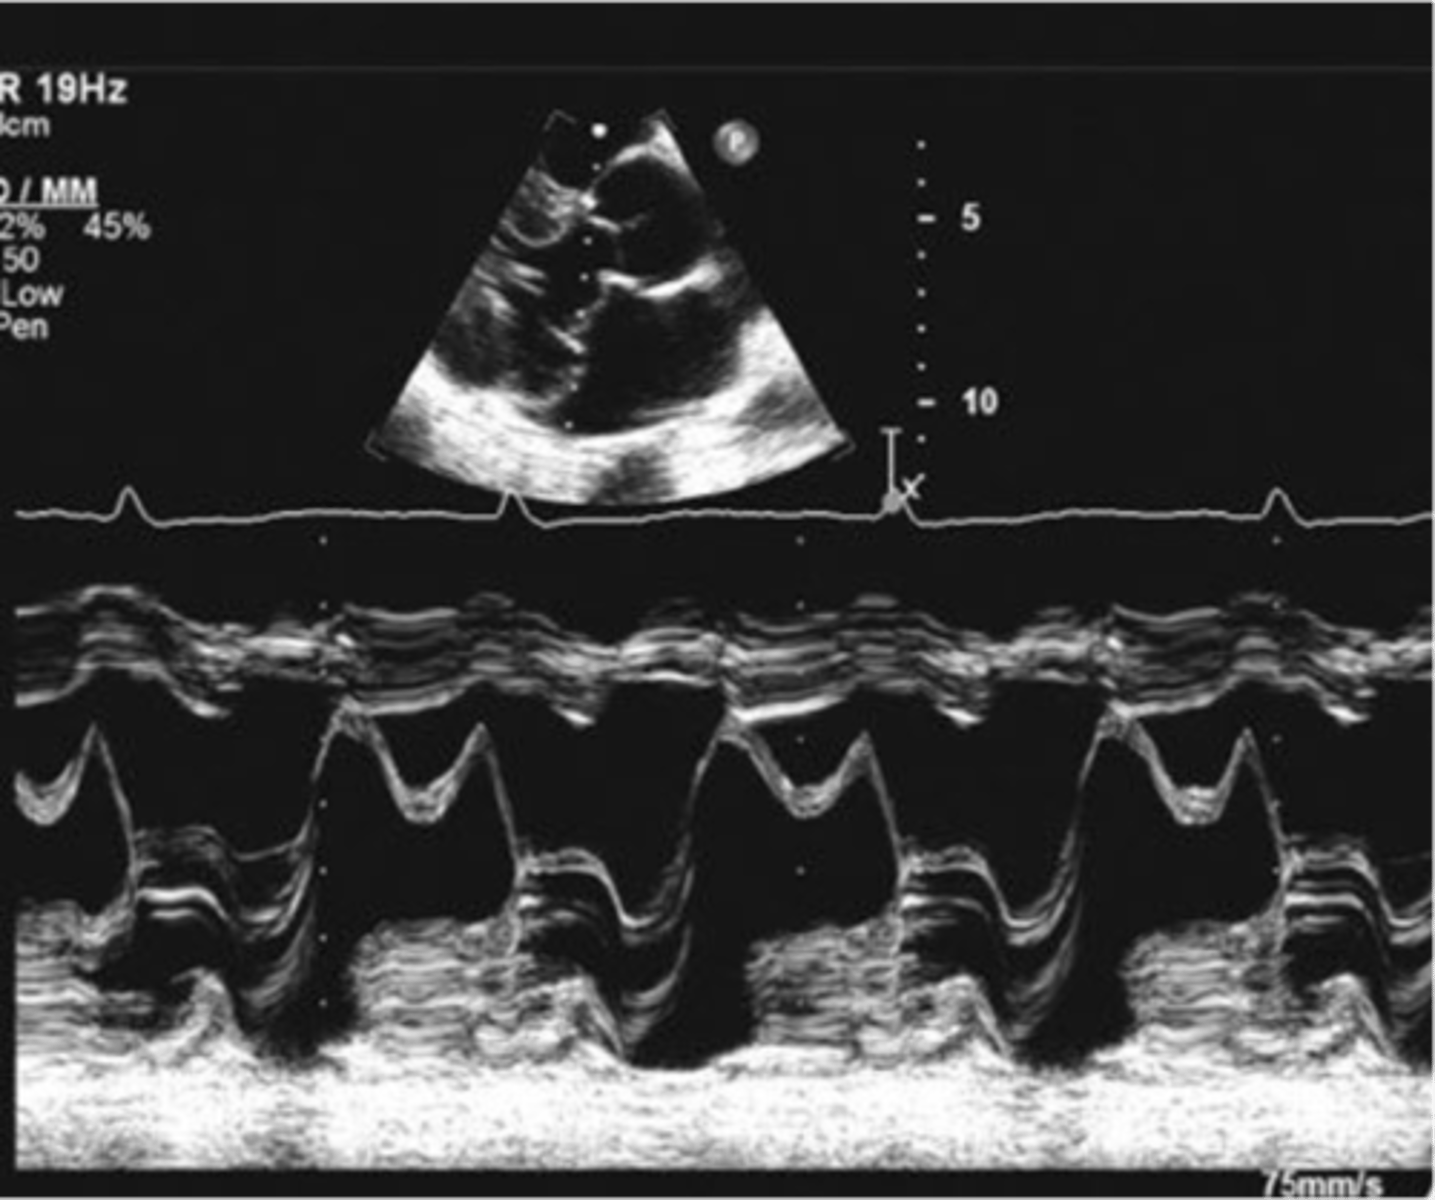

narrowing of the MV orifice with bright band of echoes in 2D and M-mode; thickening of AML and PML with anterior motion of PML; LA dilation and increased pressure; hockey puck appearance; decreased E-F slope and D-E excursion with diastolic doming

mitral valve stenosis

D-E excursion

rapid diastolic opening (1.8-2.8cm)

E-F slope

motion of AML during diastole (70-150mm/s)